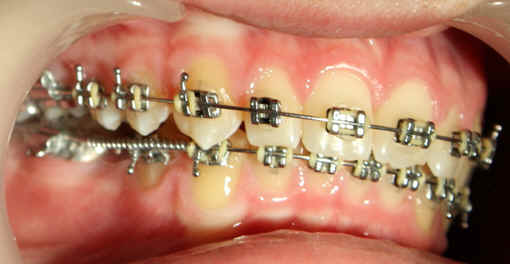

Intra-op 2009/09/10 U wire .018, L .020